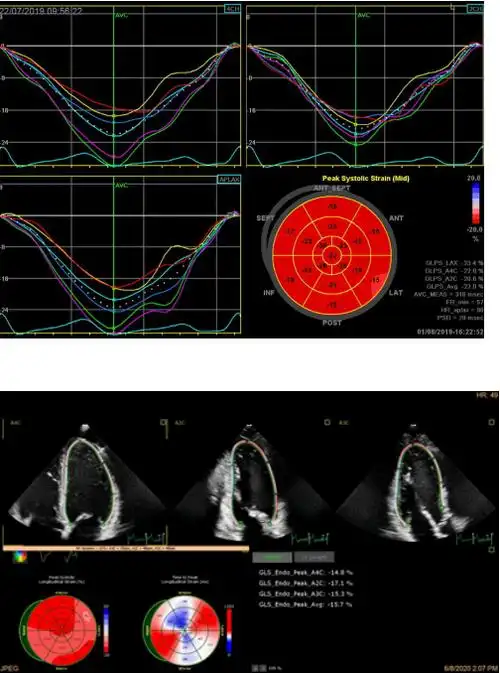

江勇: 【2020学术荟萃】人工智能在超声心动图的应用及进展 · 365